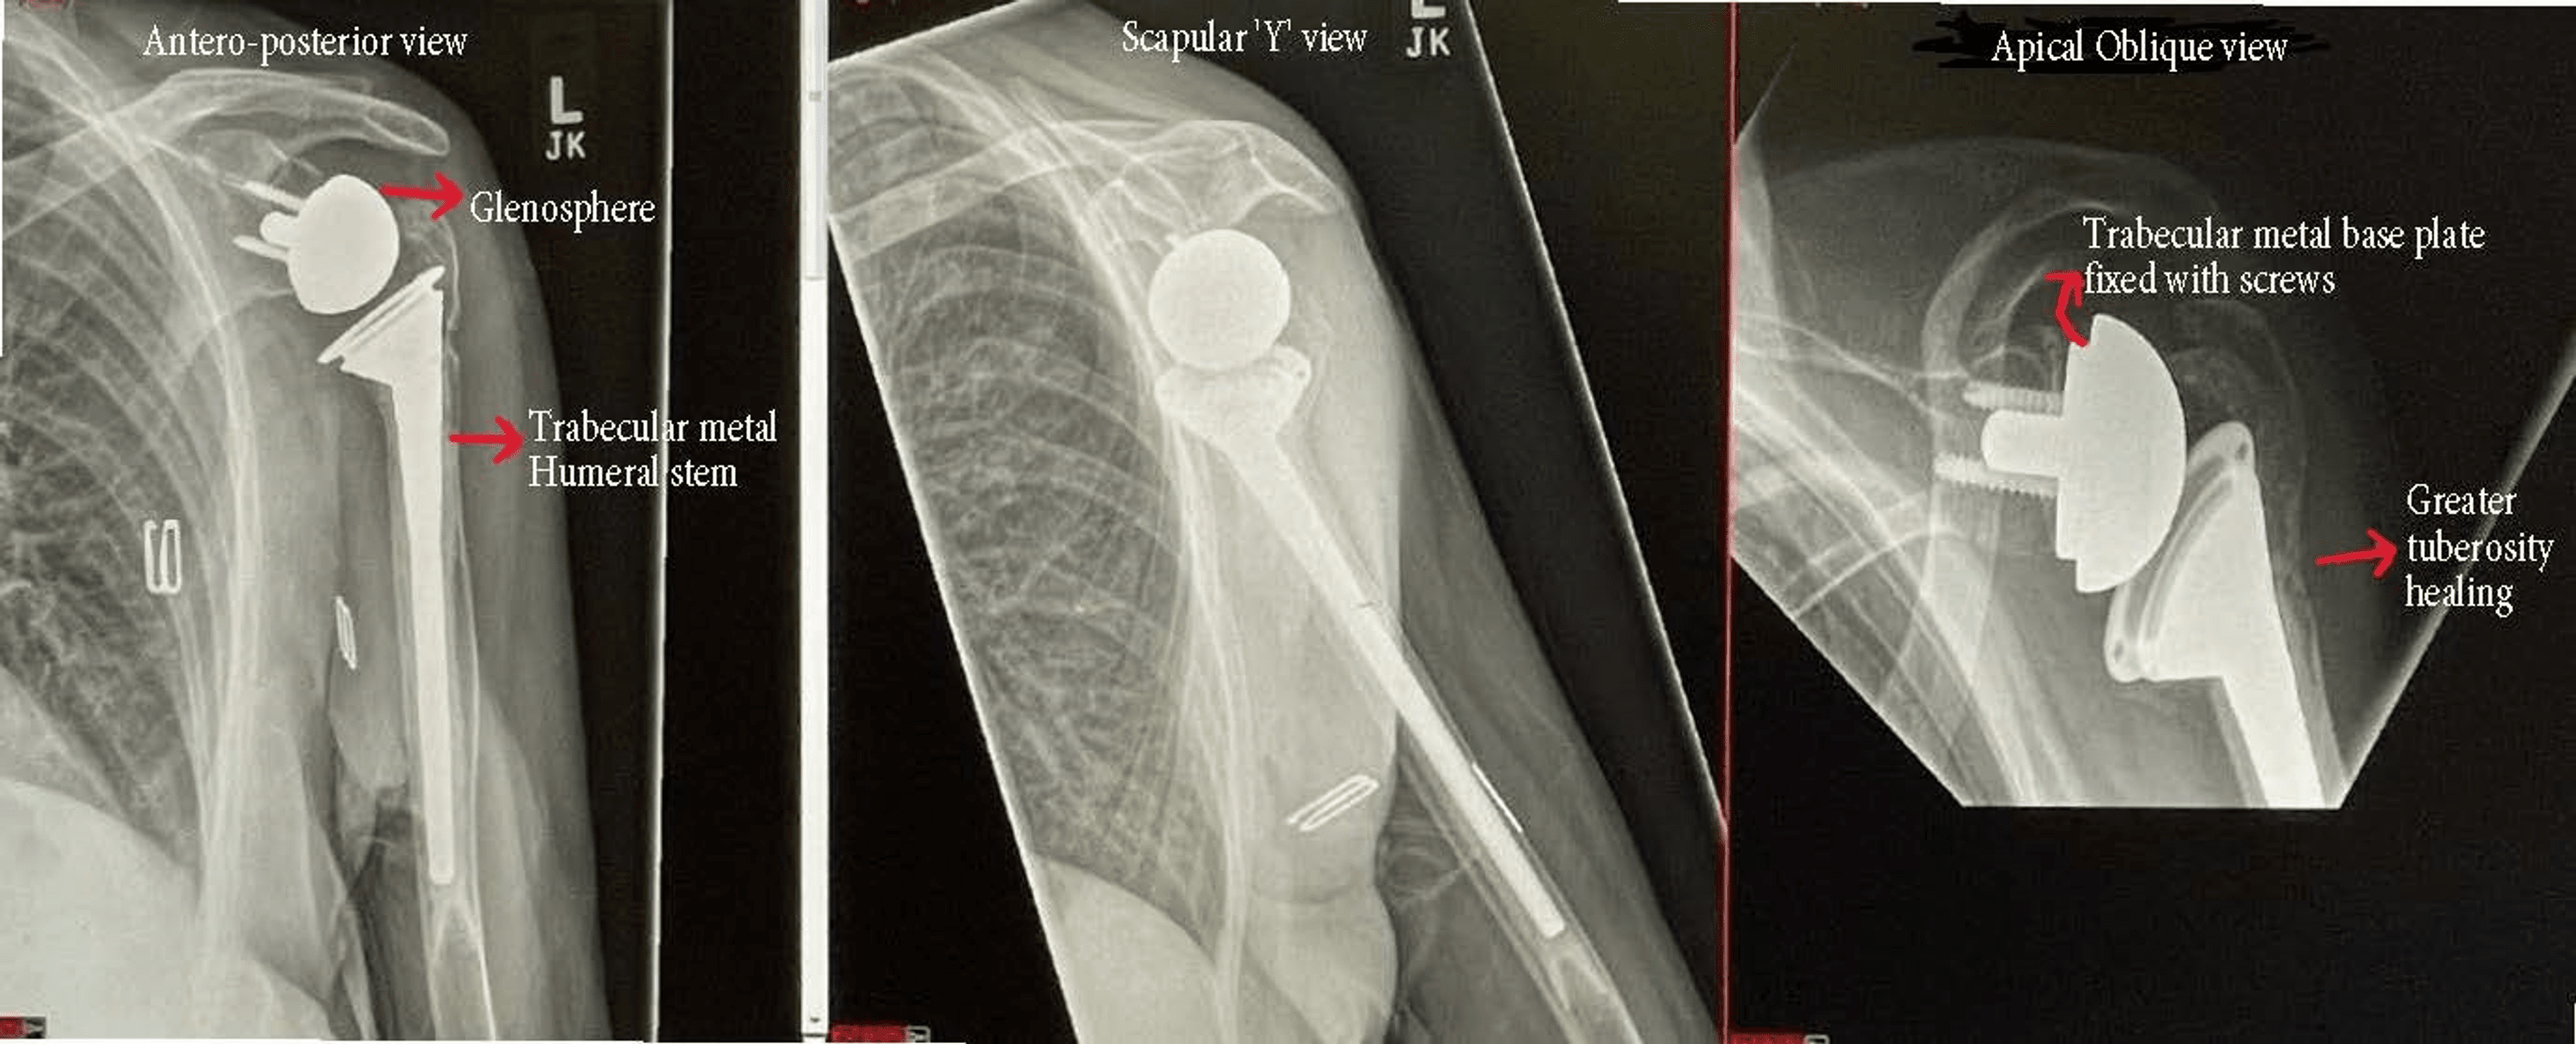

From www.cureus.com

Cureus Reverse Shoulder Arthroplasty for Acute Proximal Humerus History Of Shoulder Arthroplasty Perform a historical review of the development of reverse shoulder arthroplasty (rsa) with analysis of biomechanical features of. 77 the procedure was performed for tuberculosis of. Most arthroplasty systems can be classified as unconstrained,. The first documented shoulder arthroplasty was performed in 1893 by dr. The first articular metal prosthesis was implanted in the shoulder more than 120 years ago.. History Of Shoulder Arthroplasty.